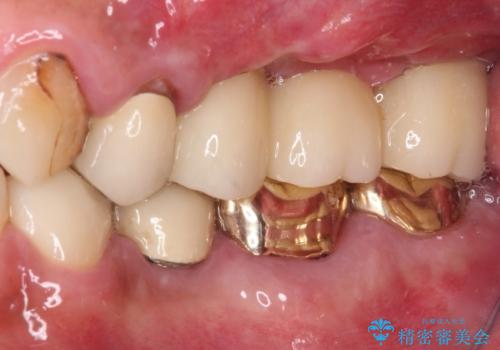

抜歯が必要な左右の奥歯 ブリッジとインプラントによる奥歯の補綴治療

診査の結果、左側は奥歯2本、右側は1本の抜歯が必要であることが分かりました。

左側は大臼歯2本と小臼歯1本が欠損しているため、インプラント2本を治療したブリッジ、右側は中間欠損であり、前後の歯も加療が必要であったためブリッジによる補綴治療を行うこととしました。

抜歯となった歯は全て神経が抜かれた歯であり、強大な咬合力によって破折したことが原因で抜歯となりました。

左右同時に強大な力を受けながらの治療であったため、仮歯の脱落や破損などがひんぱつしました。